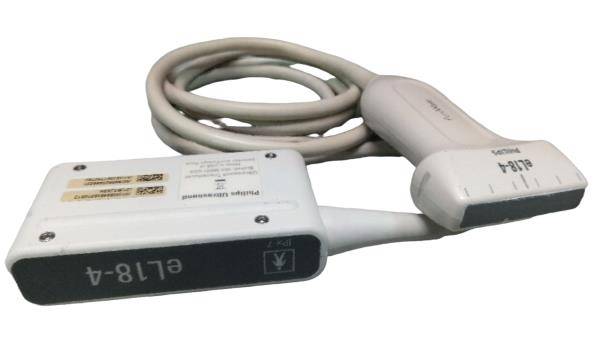

The SONOSITE TITAN OB/GYN ultrasound offers state-of-the-art imaging technology. This device uses advanced algorithms to provide clear, high-resolution images. It includes two probes: a 1-C60 convex and a 1-ICT transvaginal probe, ensuring versatility in different obstetric and gynecological applications. Because of its compact design, the SONOSITE TITAN is perfect for both hospital and remote settings, making it an ideal choice for healthcare providers.